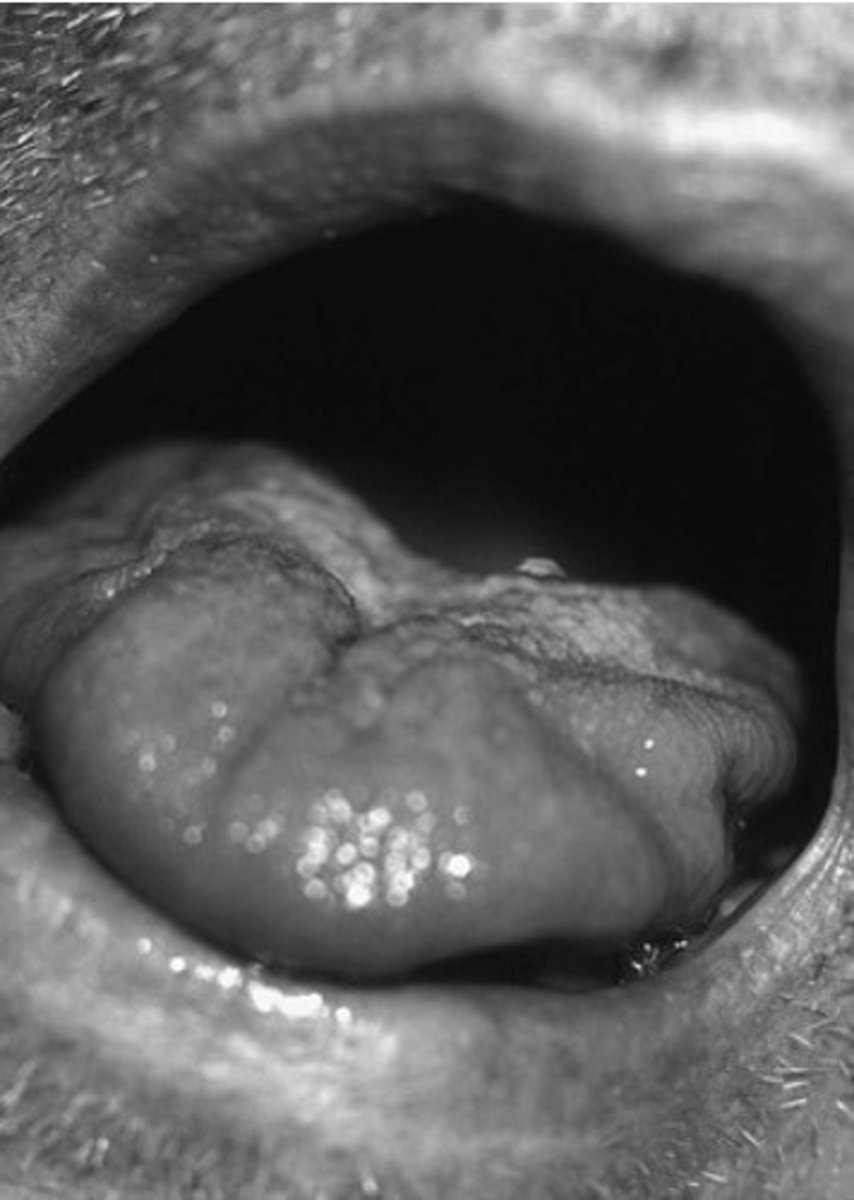

Indicate the pharynx and the hyoid bone.

A,B

Aspiration happens when a bolus passes through

D